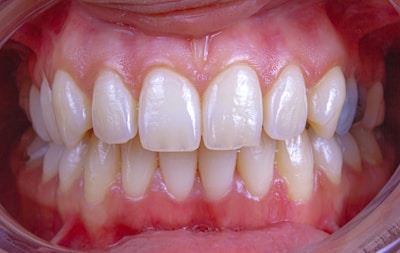

Orthodontie

Alignement des dents et des mâchoires pour un sourire harmonieux et fonctionnel.

Traitements modernes, confortables et adaptés à chaque âge.